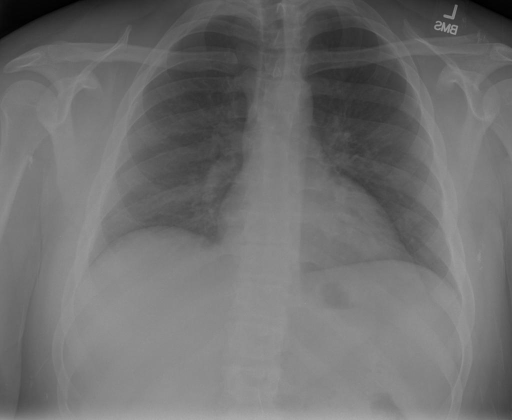

|X光影像|诊疗报告(医生)|XrayGLM|

|:-|:-|:-|

||X光图片显示没有扭曲的区域、可疑的骨质不透明度或胸腺积液。心脏大小轻微增大,但非常稳定。此外,没有气胸的证据,肺野也正常。总体来说,X光片显示没有急性心脏异常,但要注意轻微的心脏扩大。|X光片显示,心脏大小正常。肺部和纵隔轮廓清晰,没有气胸或胸腔积液的证据。骨骼结构完整,没有任何急性异常。|